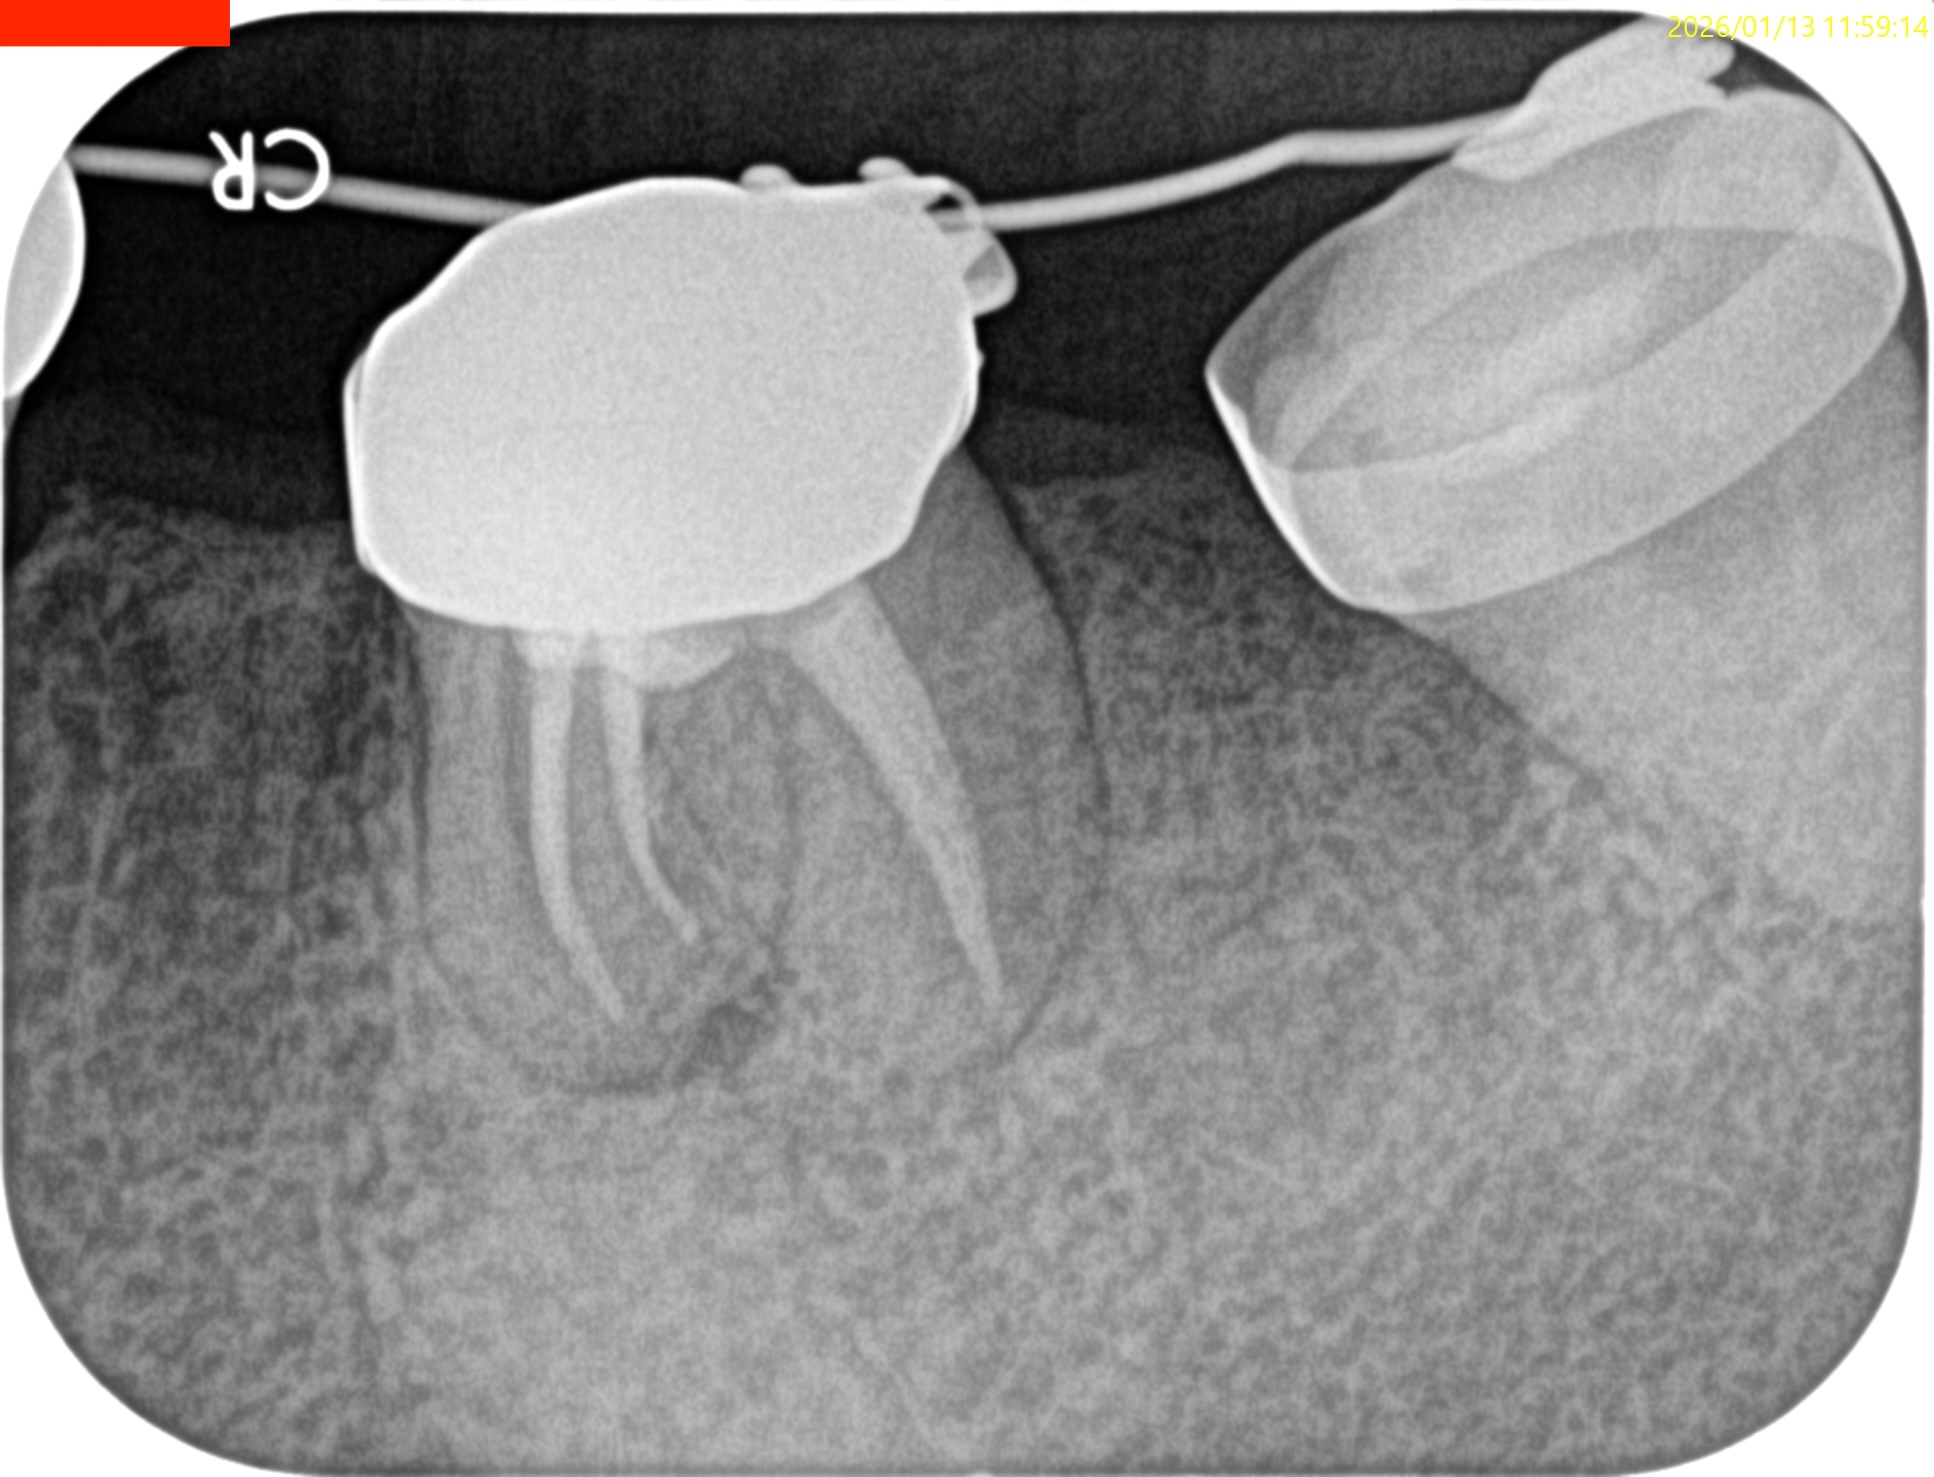

#19 Re-RCT 1yr recall(2026.1.13)

#19

MB

ML

D

術前に大きな根尖病変が存在していたM根のそれは消失はしていないが大幅に縮小し、

術前に根尖病変がなく再根管形成・充填しなかったD根はやはり依然として根尖病変はできていない。

このケースでも

Selective Root Canal Retreatmentが奏功している。

ということで根尖病変は完全消失はしていないのでまた1年後に経過を見せてもらうことになった。